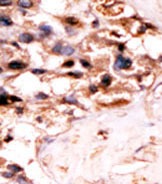

Supportive validation

- Submitted by

- Acris Antibodies GmbH (provider)

- Main image

- Experimental details

- Formalin-fixed and paraffin-embedded human cancer tissue´(hepatocarcinoma) reacted with the primary antibody, which was peroxidase-conjugated to the secondary antibody, followed by DAB staining. This data demonstrates the use of this antibody for immunohistochemistry; clinical relevance has not been evaluated.